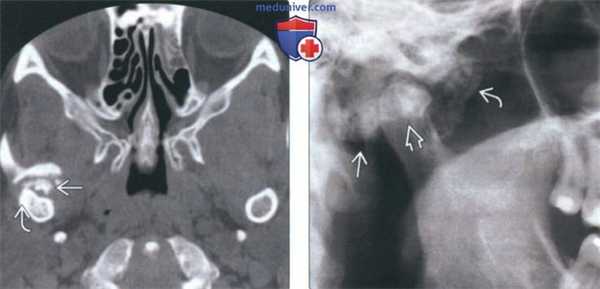

(Слева) На сагиттальной КЛКТ визуализируется крупная остеохондрома правого венечного отростка, имеющая луковицеобразную (или грибовидную) форму. Опухоль препятствует открыванию рта, упираясь в скуловой отросток верхней челюсти. Дифференциально-диагностический ряд включает гиперплазию венечного отростка, но при гиперплазии венечный отросток сохраняет свою форму.

(Справа) На корональной КЛКТ у этого же пациента определяется луковицеобразное увеличение венечного отростка за счет остеохондромы. (Слева) На аксиальной КЛКТ у этого же пациента визуализируется остеохондрома правого венечного отростка (сравните с неизмененным левым венечным отростком).

(Справа) На сагиттальной КЛКТ левого мыщелка на его передней поверхности визуализируется большая луковицеобразная остеохондрома. Внутренняя часть опухоли продолжается в неизмененную трабекулярную кость мыщелка. Определяется ремоделирование височной кости как приспособительная реакция к опухоли. (Слева) На трехмерной реконструкции (вид сбоку) у этого же пациента изнутри от скуловой дуги и выше нее визуализируется большая остеохондрома мыщелка.

(Справа) На корональной реформатированной КЛКТ у этого же пациента визуализируется большая луковицеобразная осге-охондрома мыщелка. Внутренняя часть опухоли образована трабекулярной костью с более выраженным участком склероза в центре. Обратите внимание на тонкий кортикальный слой на суставной поверхности.